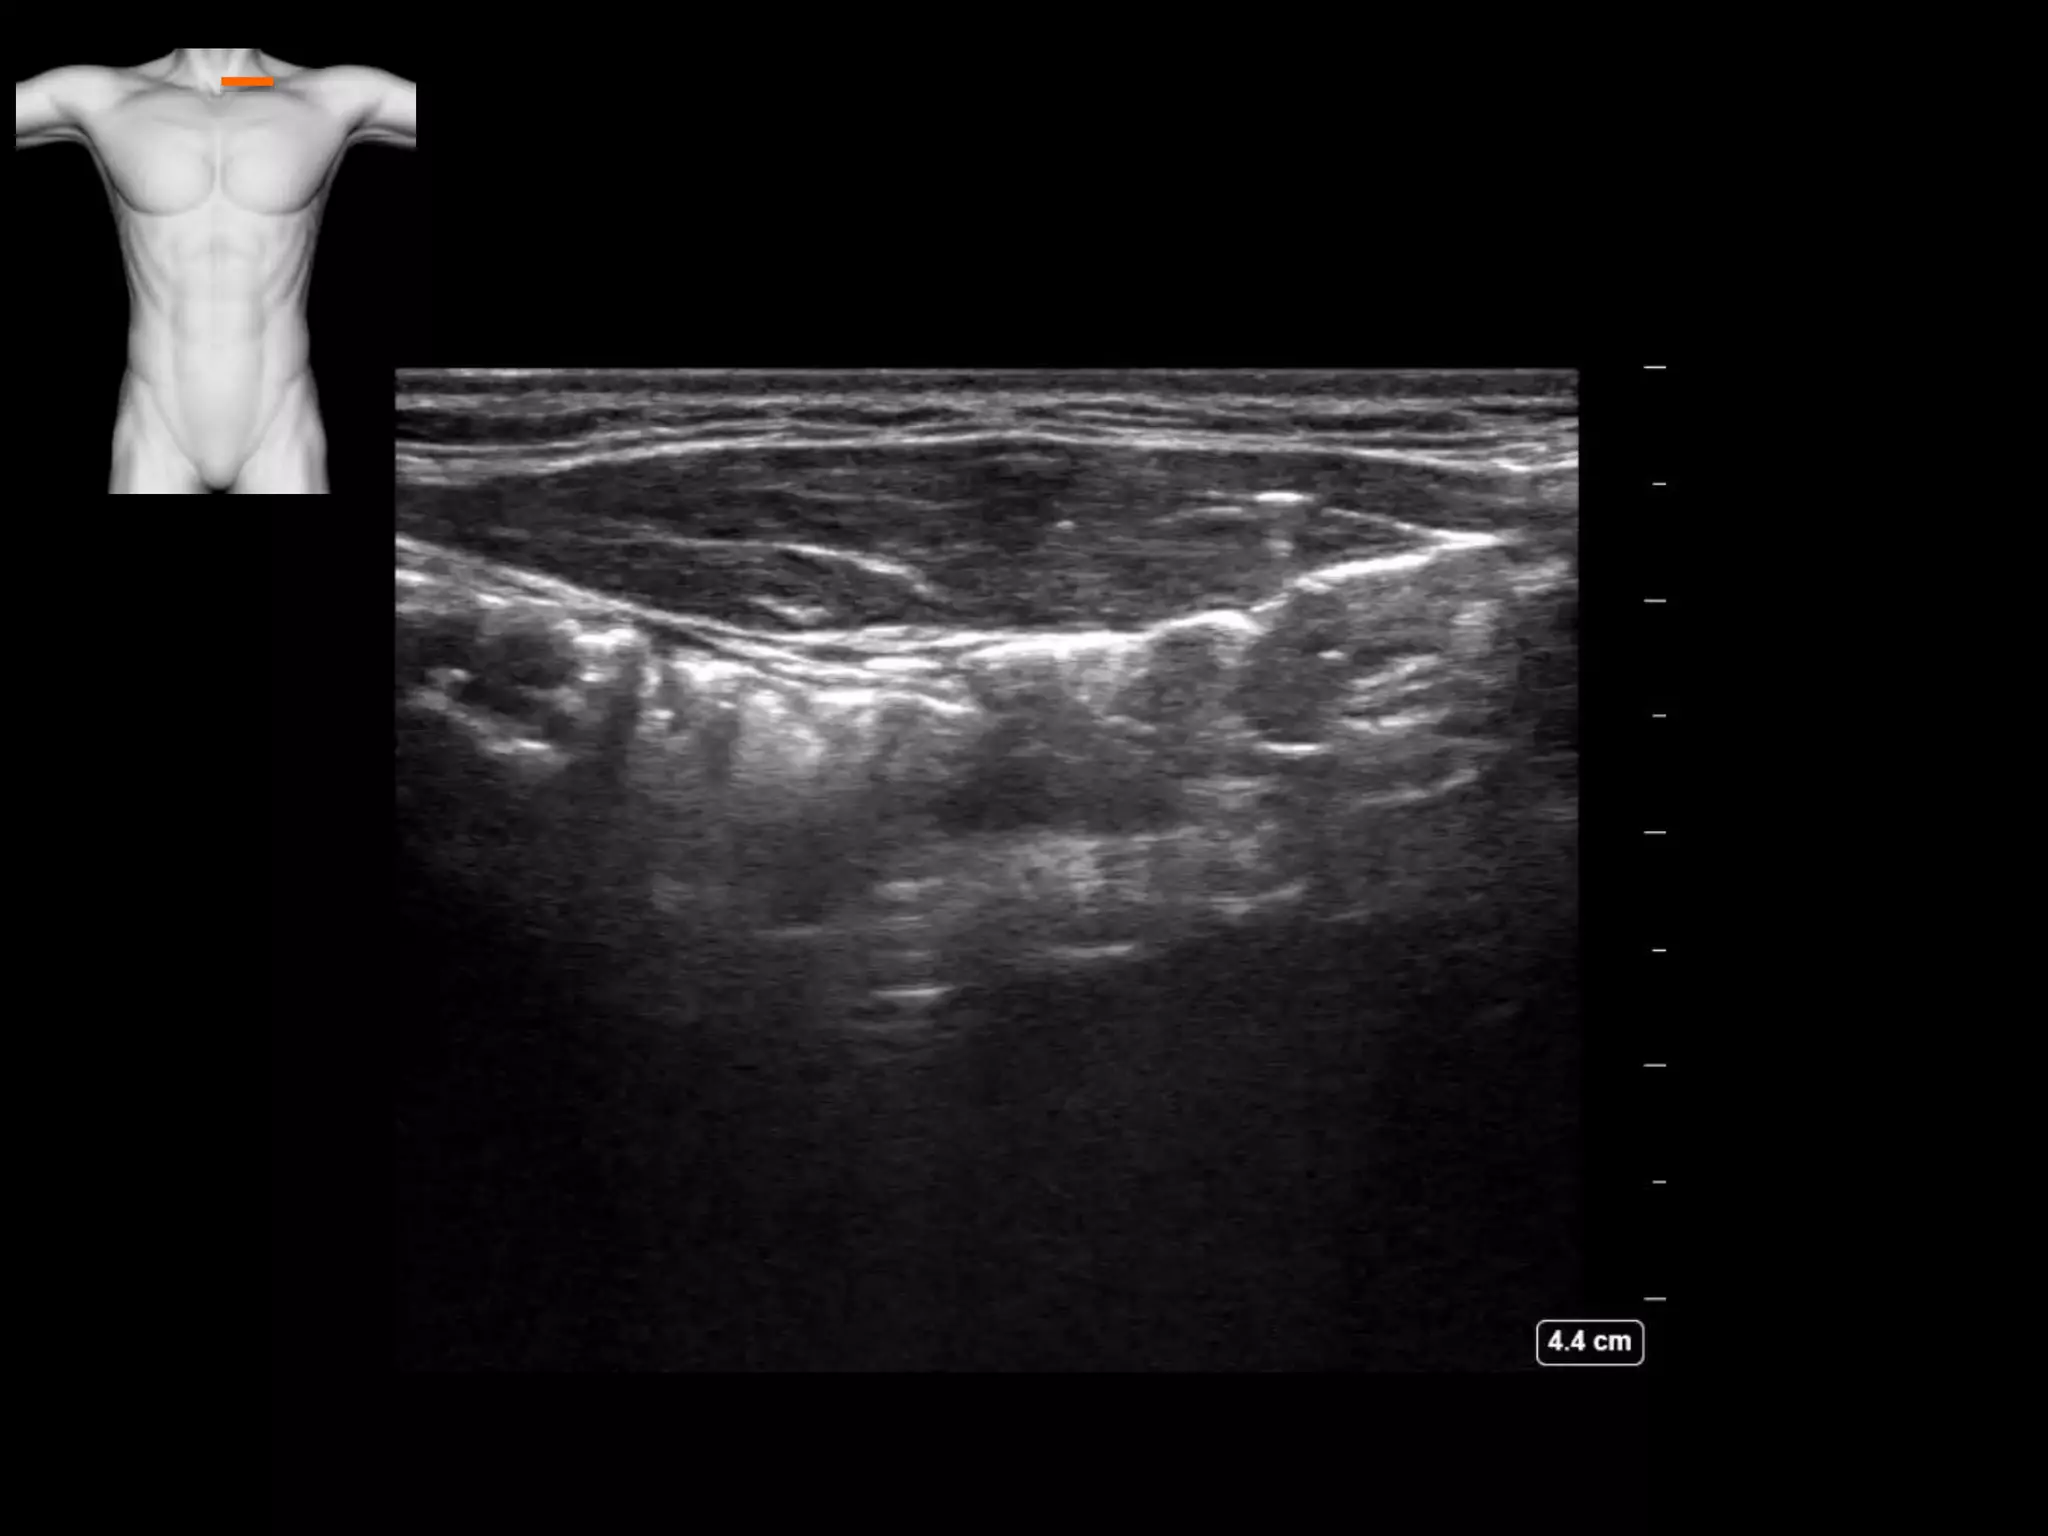

Subcutanous emphysema

• There is air lying between the facial planes

• No ribs are seen

• This is surgical emphysema obscuring true

interpretation of the underlying lung